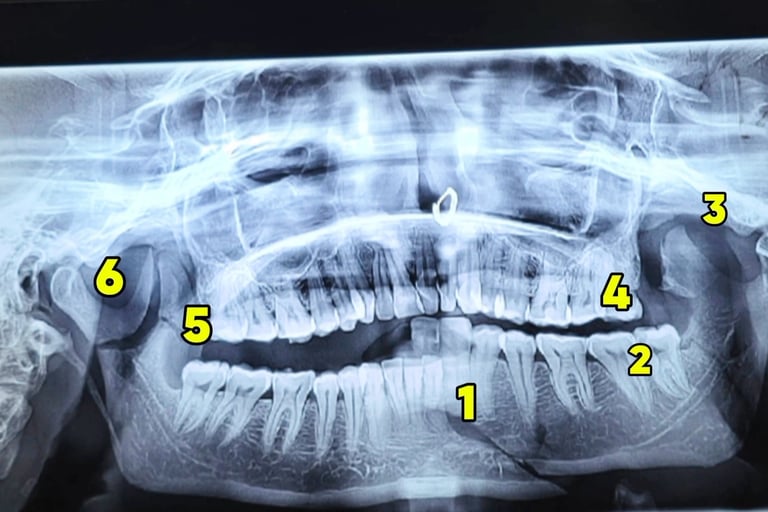

Radiographic Diagnosis: Orthopantomogram (OPG) was performed, which revealed multiple mandibular fractures involving:

Right angle region

Parasymphysis region

Bilateral condylar involvement

Coronoid fracture

Total of 6 fracture segments